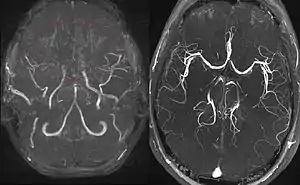

Moyamoya disease is a disease in which certain arteries in the brain are constricted. Blood flow is blocked by constriction and blood clots (thrombosis).[1] A collateral circulation develops around the blocked vessels to compensate for the blockage, but the collateral vessels are small, weak, and prone to bleeding, aneurysm and thrombosis. On conventional MR angiography, these collateral vessels have the appearance of a "puff of smoke" (described as "もやもや (moyamoya)" in Japanese).[1]

Right: healthy patient, for comparison.

Magnetic resonance angiography (MRA) is also useful in diagnosing the disease with good correlation with Suzuki's grading system.[12]